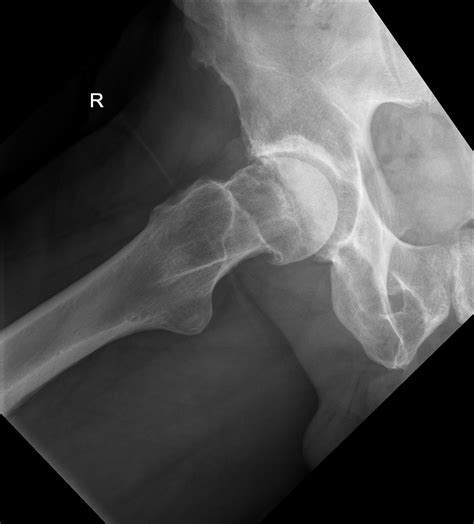

In patients with Cam Impingement, the shape of the femoral head is not perfectly round. Instead, it has an abnormal bony growth, often referred to as a "cam" lesion. Because this bone is irregular, it cannot rotate smoothly within the socket. As you move, especially during hip flexion or internal rotation, this extra bone bumps into the rim of the socket, pinching the labrum and causing damage to the articular cartilage.

If you suspect you have Cam Impingement Hip, a physical examination is the first step. An orthopedic specialist will perform specific tests, such as the FADIR test (Flexion, Adduction, Internal Rotation), which is designed to reproduce the impingement and pain. Following this, imaging is usually required to confirm the diagnosis.

• X-rays: Standard views help the doctor visualize the shape of the femur and the degree of the bony prominence.